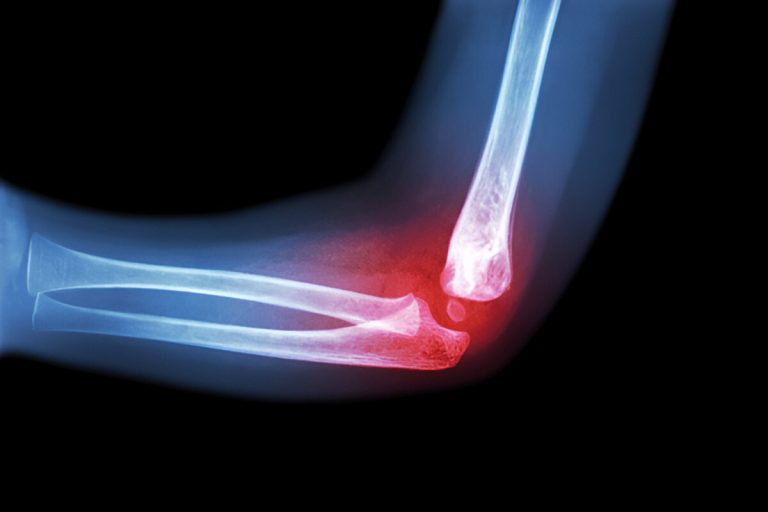

The lateral collateral ligament (LCL) of the elbow — also called the radial collateral ligament — is a key stabilizing structure on the outer (lateral) side of the elbow joint. It connects the lateral humerus (upper arm bone) to the radius (forearm bone) and helps resist varus stress, which pushes the forearm toward the body. The LCL also works with surrounding structures to maintain elbow stability during motion and protect against dislocation.

• MRI to confirm ligament damage

• X-rays to evaluate for bone or joint abnormalities